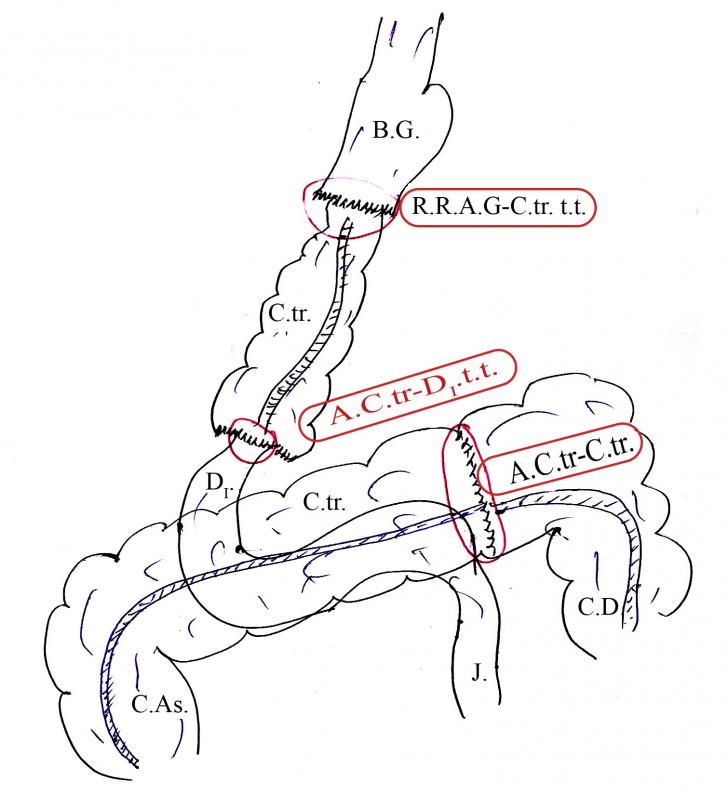

mult mai rare comparativ cu psihozele adultilor. Aceast&#Citeste mai mult « 6999 cuvinte, 14 pag. » TRATAMENTUL CHIRURGICAL AL FISTULELOR dupa

RECONVERSIUNEA DUODENULUI PRIN PROCEDEUL MORONEY Interpunerea unui

segment de colon transvers intre bonturile gastric si duodenal.

FISTULA GASTRO-COLONICA TRANSVERS. (Fig. 48.)

Citeste mai mult « 1854 cuvinte, 4 pag. » Tratamentul medicamentos si chirurgical al fibromului uterin